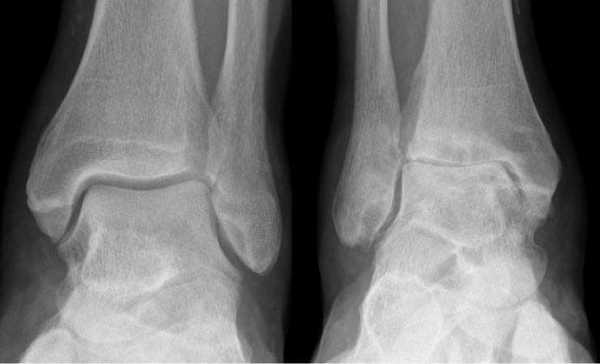

Остеоартроз голеностопного сустава на рентгене.

Основной причиной артроза голеностопного сустава (крузартроза) является травматическое повреждение его анатомических структур — таранной и большеберцовой кости, внутренней или наружной лодыжек. Реже болезнь развивается вследствие поражения голеностопа ревматоидным артритом. И еще реже артроз возникает спонтанно, в результате дегенеративно-дистрофических изменений в хрящевой и костной тканях.

Остеоартроз левого(справа на снимке) голеностопного сустава

Рентгенологические стадии по Kellgren и Lawrence:

- 0 — полное отсутствие рентгенологических признаков;

- І — кистовидные изменения костной ткани, субхондральный линейный остеосклероз, краевые остеофиты небольшого размера;

- ІІ — сужение суставной щели, более выраженный остеосклероз;

- ІІІ — массивный субхондральный остеосклероз, сильное сужение суставной щели, остеофиты большого размера;

- ІV — массивные остеофиты, деформация эпифизов костей, практически полное отсутствие суставной щели.

- Начальная стадия. Характеризуется поражением только суставных хрящей. На рентгенограммах может визуализироваться незначительное сужение суставной щели, которое заметно лишь при сравнении с симметричным суставом.

- Стадия выраженных изменений. В дегенеративно-деструктивный процесс вовлекаются кости с развитием субхондрального остеосклероза. При рентгенографии выявляют краевые остеофиты и неравномерное сужение суставной щели как минимум на 50%.

- Стадия ярко выраженных изменений. Проявляется выраженным ограничением подвижности голеностопа. На рентгенограммах видны большие участки остеосклероза, массивные остеофиты, деформация костей и нарушение конгруэнтности суставных поверхностей.

- Рентгенография. Информативна на поздних стадиях заболевания, но не всегда позволяет обнаружить ранние изменения. С помощью рентгенографии можно визуализировать субхондральный остеосклероз, остеофиты, костные деформации, сужение суставной щели.